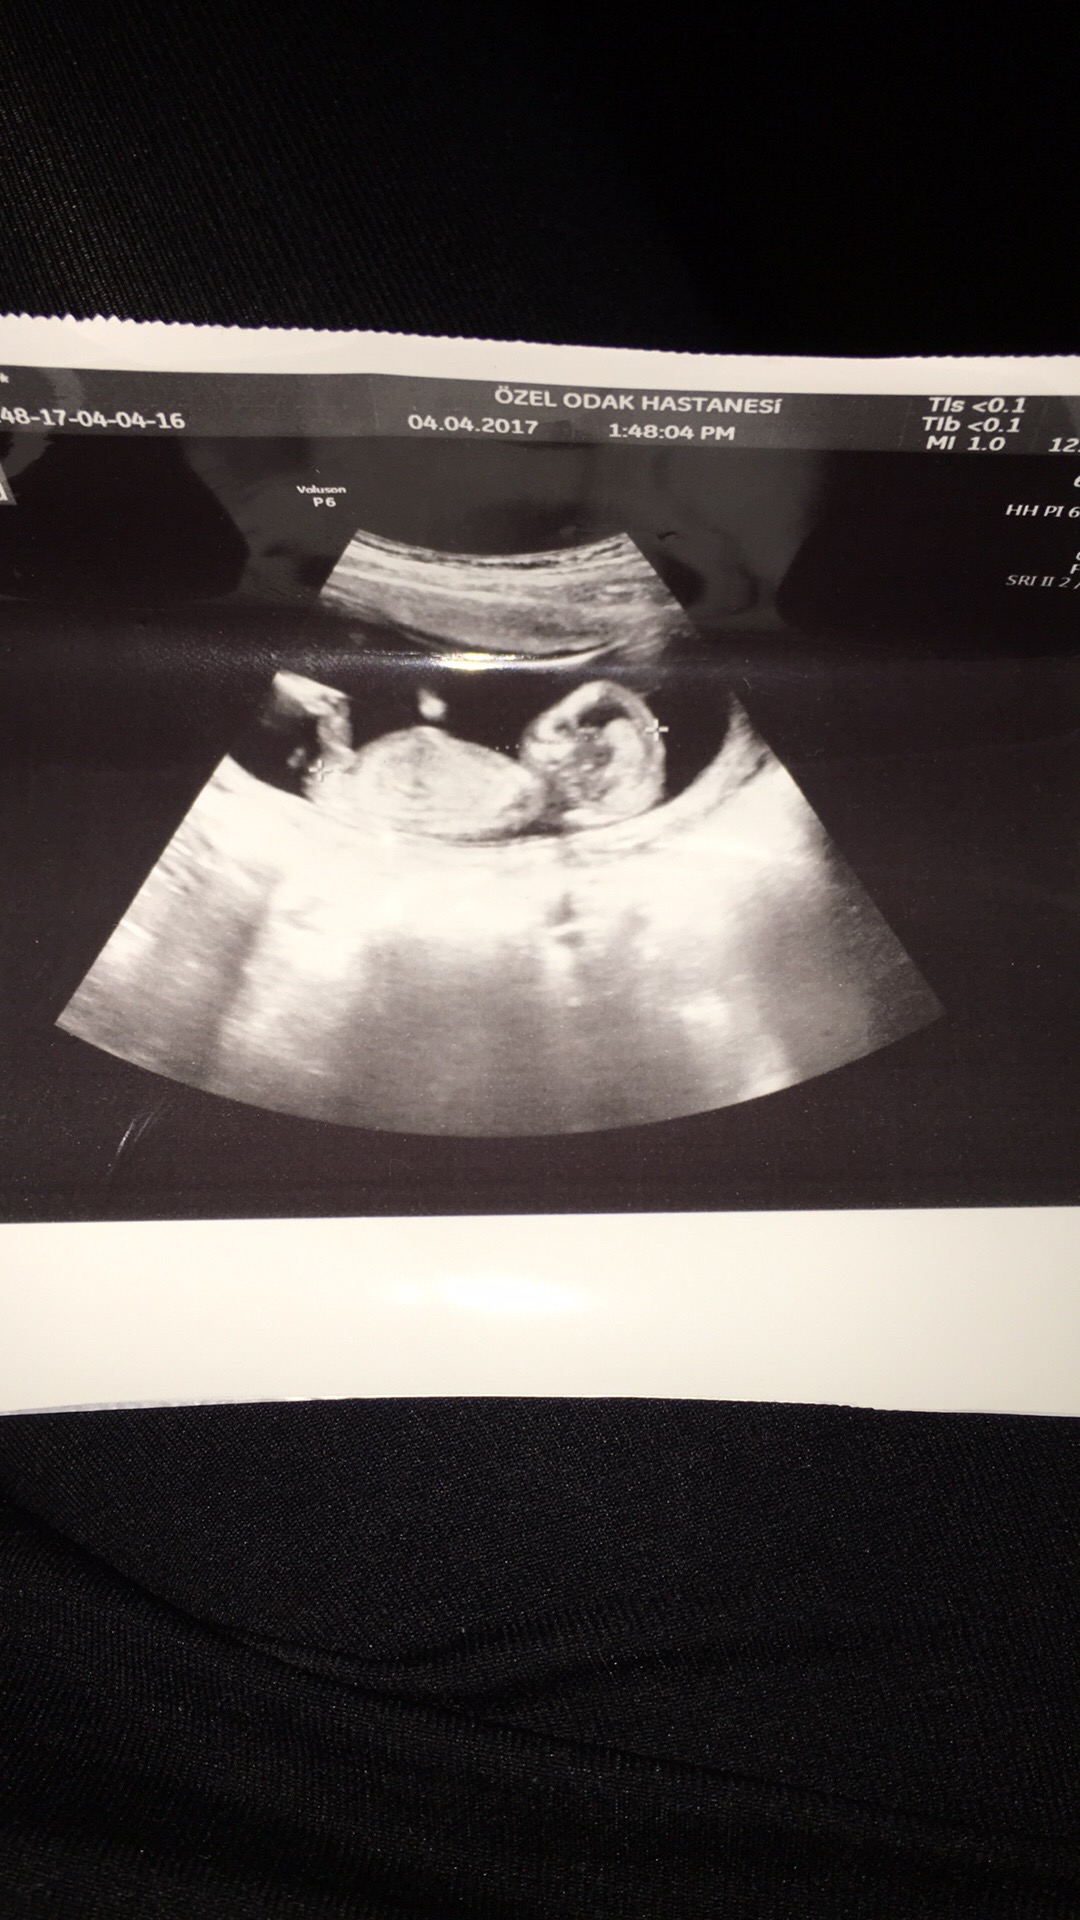

K Kocakafa Yeni Üye Üye 7 Nisan 2017 #233 Bizim cinsiyetımiz nedir nub teorısıne göre 14 haftalıgız Ekli dosyalar 3A8C3758-90C8-4C0B-ACBF-DEB629D7014F.jpg 401,4 KB · Görüntüleme: 670